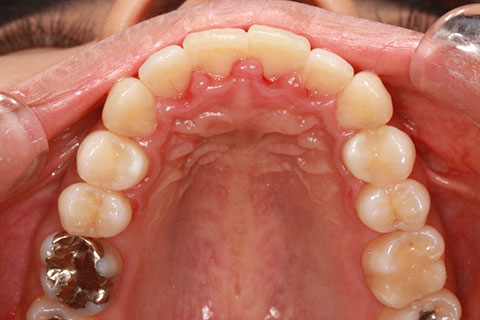

矯正期間24ヶ月

ハーフリンガル矯正3(上の歯のみ舌側矯正で治療)

治療前

治療中(開始直後)

治療中(開始半年後)

治療後

- 年齢・性別

- 25歳女性

- 治療期間

- 2年0ヶ月

- 抜歯

- 上下4番抜歯

- 治療費

- 110万円

- 備考

- 治療内容

- 施術の副作用(リスク)

- 表側矯正と比較して、力学的な操作性が複雑なため、ボーイングエフェクトを起こしやすい。